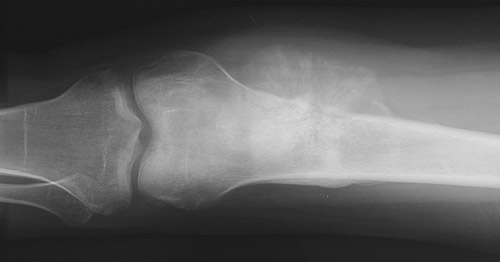

![]() | In these AP radiographs of the distal femur, an osteosarcoma involves the metaphyseal region. The tumor erodes and destroys the bone cortex, extending into soft tissue where irregular tumor bone with calcification is seen. The periosteum is being lifted off. The view below was taken 2 months later, with a greater soft tissue mass present. |